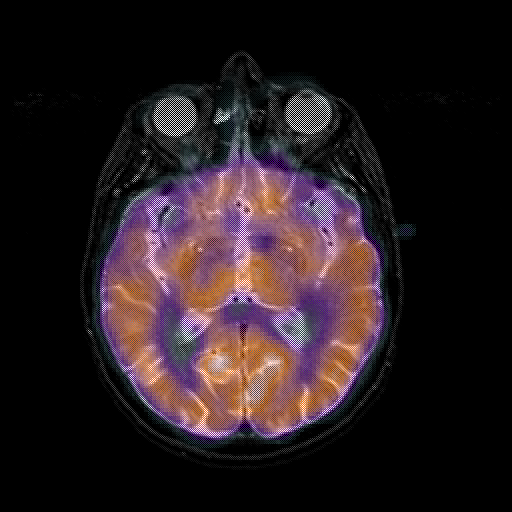

overlay 1: Slice 26

Slice 26

MRCBFCBF with

T1PDT2T1PDT2